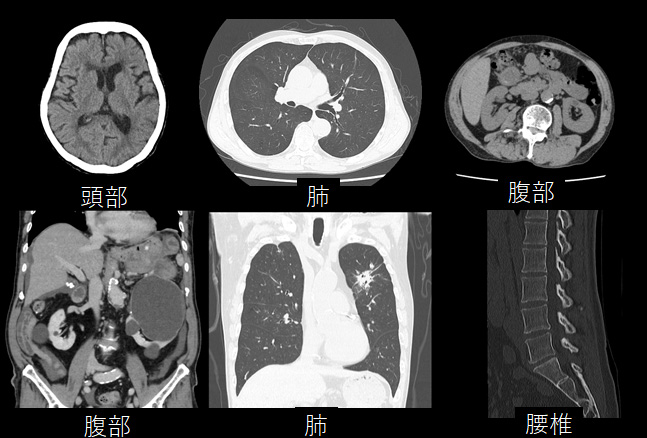

血液検査や尿検査、レントゲン検査、超音波検査などの結果より、さらに詳細に身体内部を知る必要がある際に実施されます。従来は、輪切り画像(断面画像)とも言われていましたが、装置の高性能化に伴い断面画像だけでなく、様々な方向からの画像観察が可能となりました。

さらに、特殊技術を用いることで被ばく線量の低減や造影剤量の低減を図りつつ、身体の内部をより精細に写し出すことが可能であり、様々な病気の発見に役立ちます。

頭部領域 では320列面検出器を活かした高精細画像が撮影可能

頭部領域では出血や梗塞、腫瘍などさまざまな病気が存在します。その原因となる血管の形や太さは人によって様々ですが、当院のCTと造影剤という薬剤を用いることでそれらを正確に画像化することができます。特に4D撮影という特殊な撮影を行うことで、血液の流れを見ることが可能となり血流の違いによる病気の発見にも役立ちます。